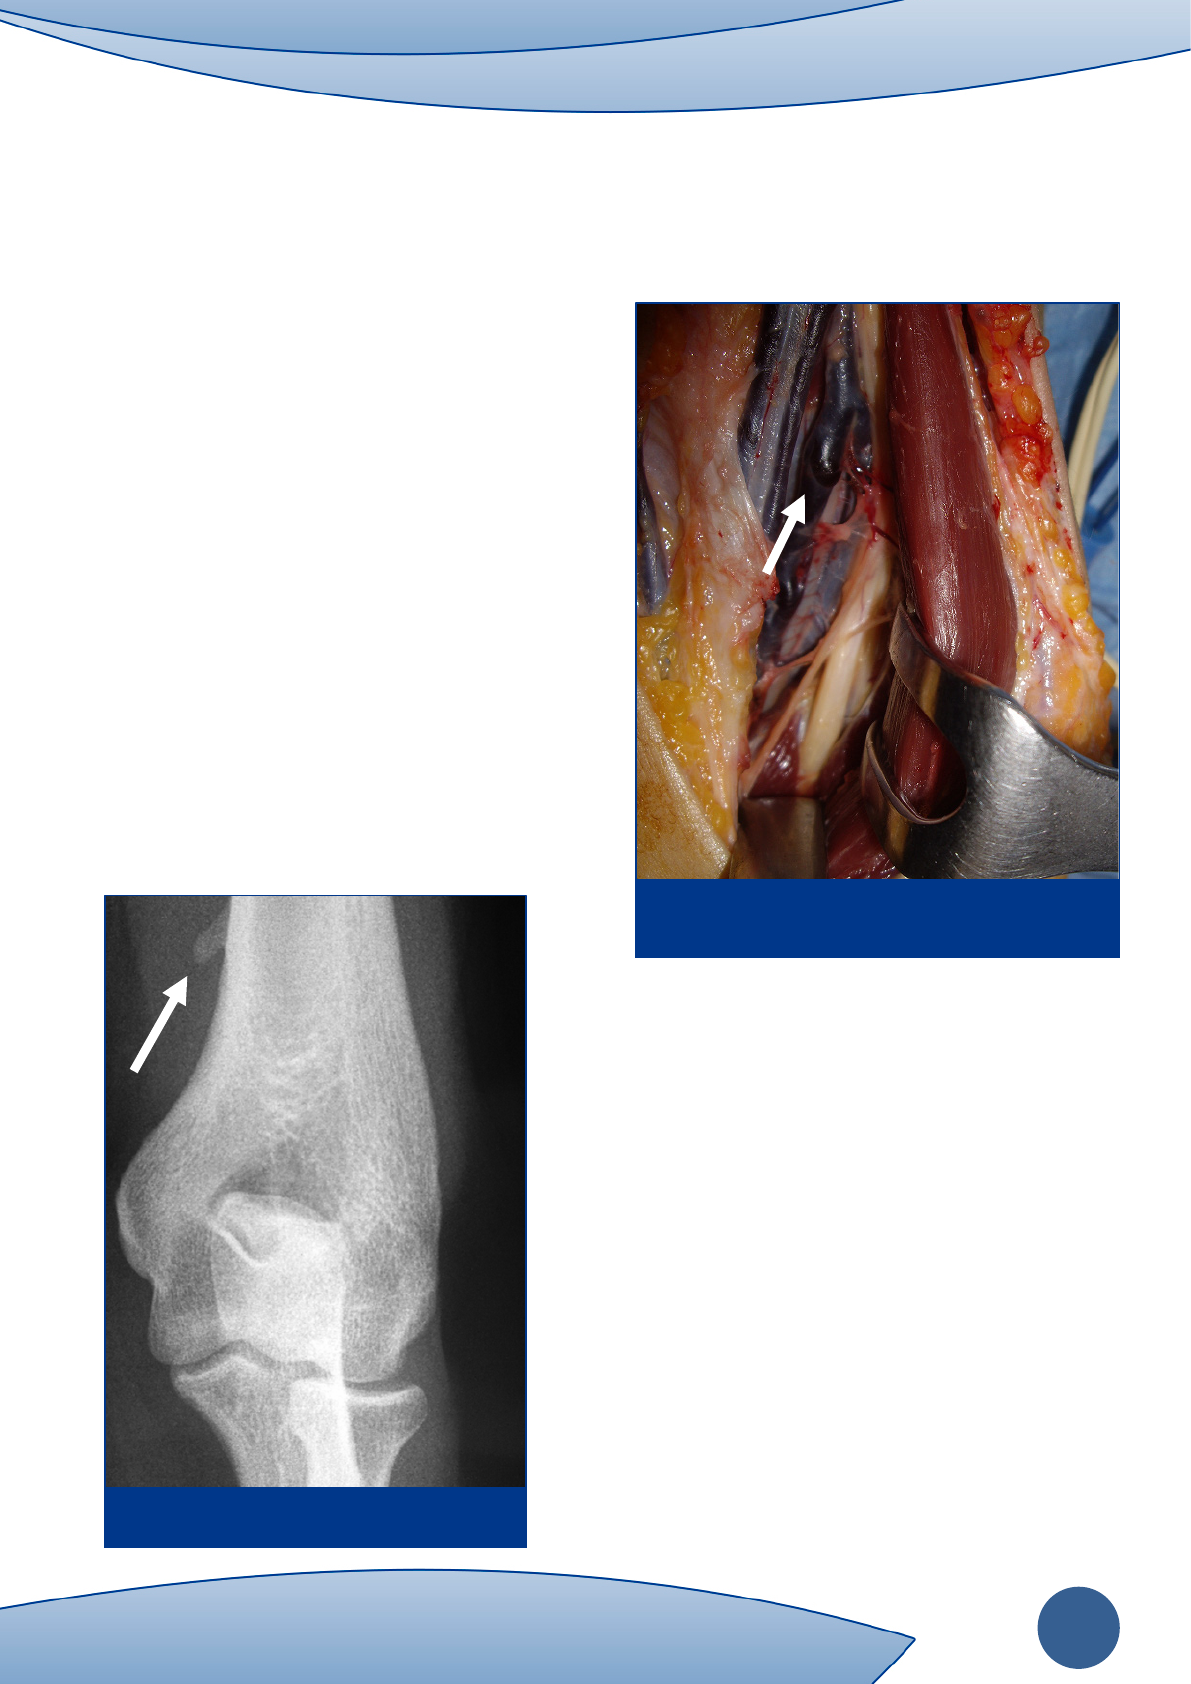

Las posibles zonas de compresión son la apófisis de

Struthers (supracondílea en la zona antero medial del

húmero distal) (Figura 1), el ligamento de Struthers (banda

fibrosa entre la apófisis y la epitróclea), la expansión

aponeurótica del bíceps sobre la musculatura

flexopronadora, el arco fibroso entre las cabezas humeral y

cubital del pronador redondo (Figura 2), o el arco fibroso

del flexor común superficial de los dedos (FSD).

Figura 1. Apófisis de Struthers.

Figura 2. Nervio mediano entre vientres del pronador

redondo.